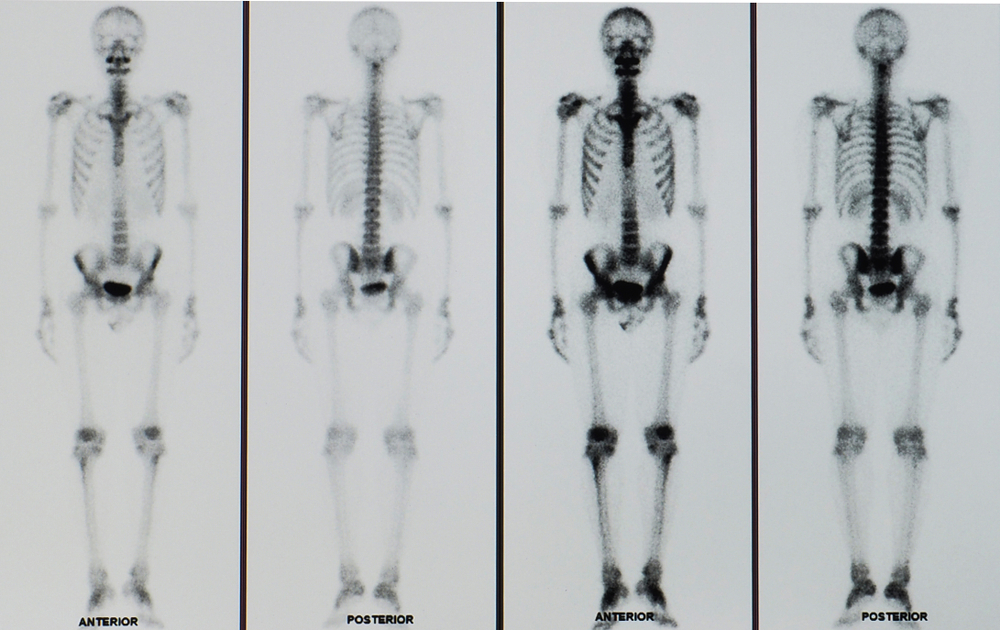

Xương cũng là một trong các cơ quan mà tế bào ung thư vòm họng thường lây lan đến. Theo đó, triệu chứng ung thư vòm họng di căn xương đầu tiên mà bệnh nhân thường nhận thấy chính là đau xương. Các cơn đau có xu hướng tồi tệ hơn vào ban đêm hoặc khi bệnh nhân đi lại, di chuyển.

Trong một số trường hợp, xương có thể yếu đến mức bị gãy (gãy xương bệnh lý) khi chỉ mới tác động nhẹ. Tình trạng này gây ra những cơn đau đột ngột và vô cùng nghiêm trọng.

Ngoài ra, ung thư vòm họng di căn xương cũng có thể chèn ép tủy sống và dẫn đến các triệu chứng như đau lưng, tê hoặc yếu tay chân, mất kiểm soát bàng quang và ruột… Khi tế bào ung thư lan đến xương, canxi ở xương sẽ giải phóng vào máu nhiều, từ đó gây tăng canxi máu. Tình trạng tăng canxi máu khiến bệnh nhân bị táo bón, đi tiểu thường xuyên, buồn ngủ, uể oải, khát nhiều, yếu cơ, lú lẫn, hôn mê hoặc thậm chí suy thận.